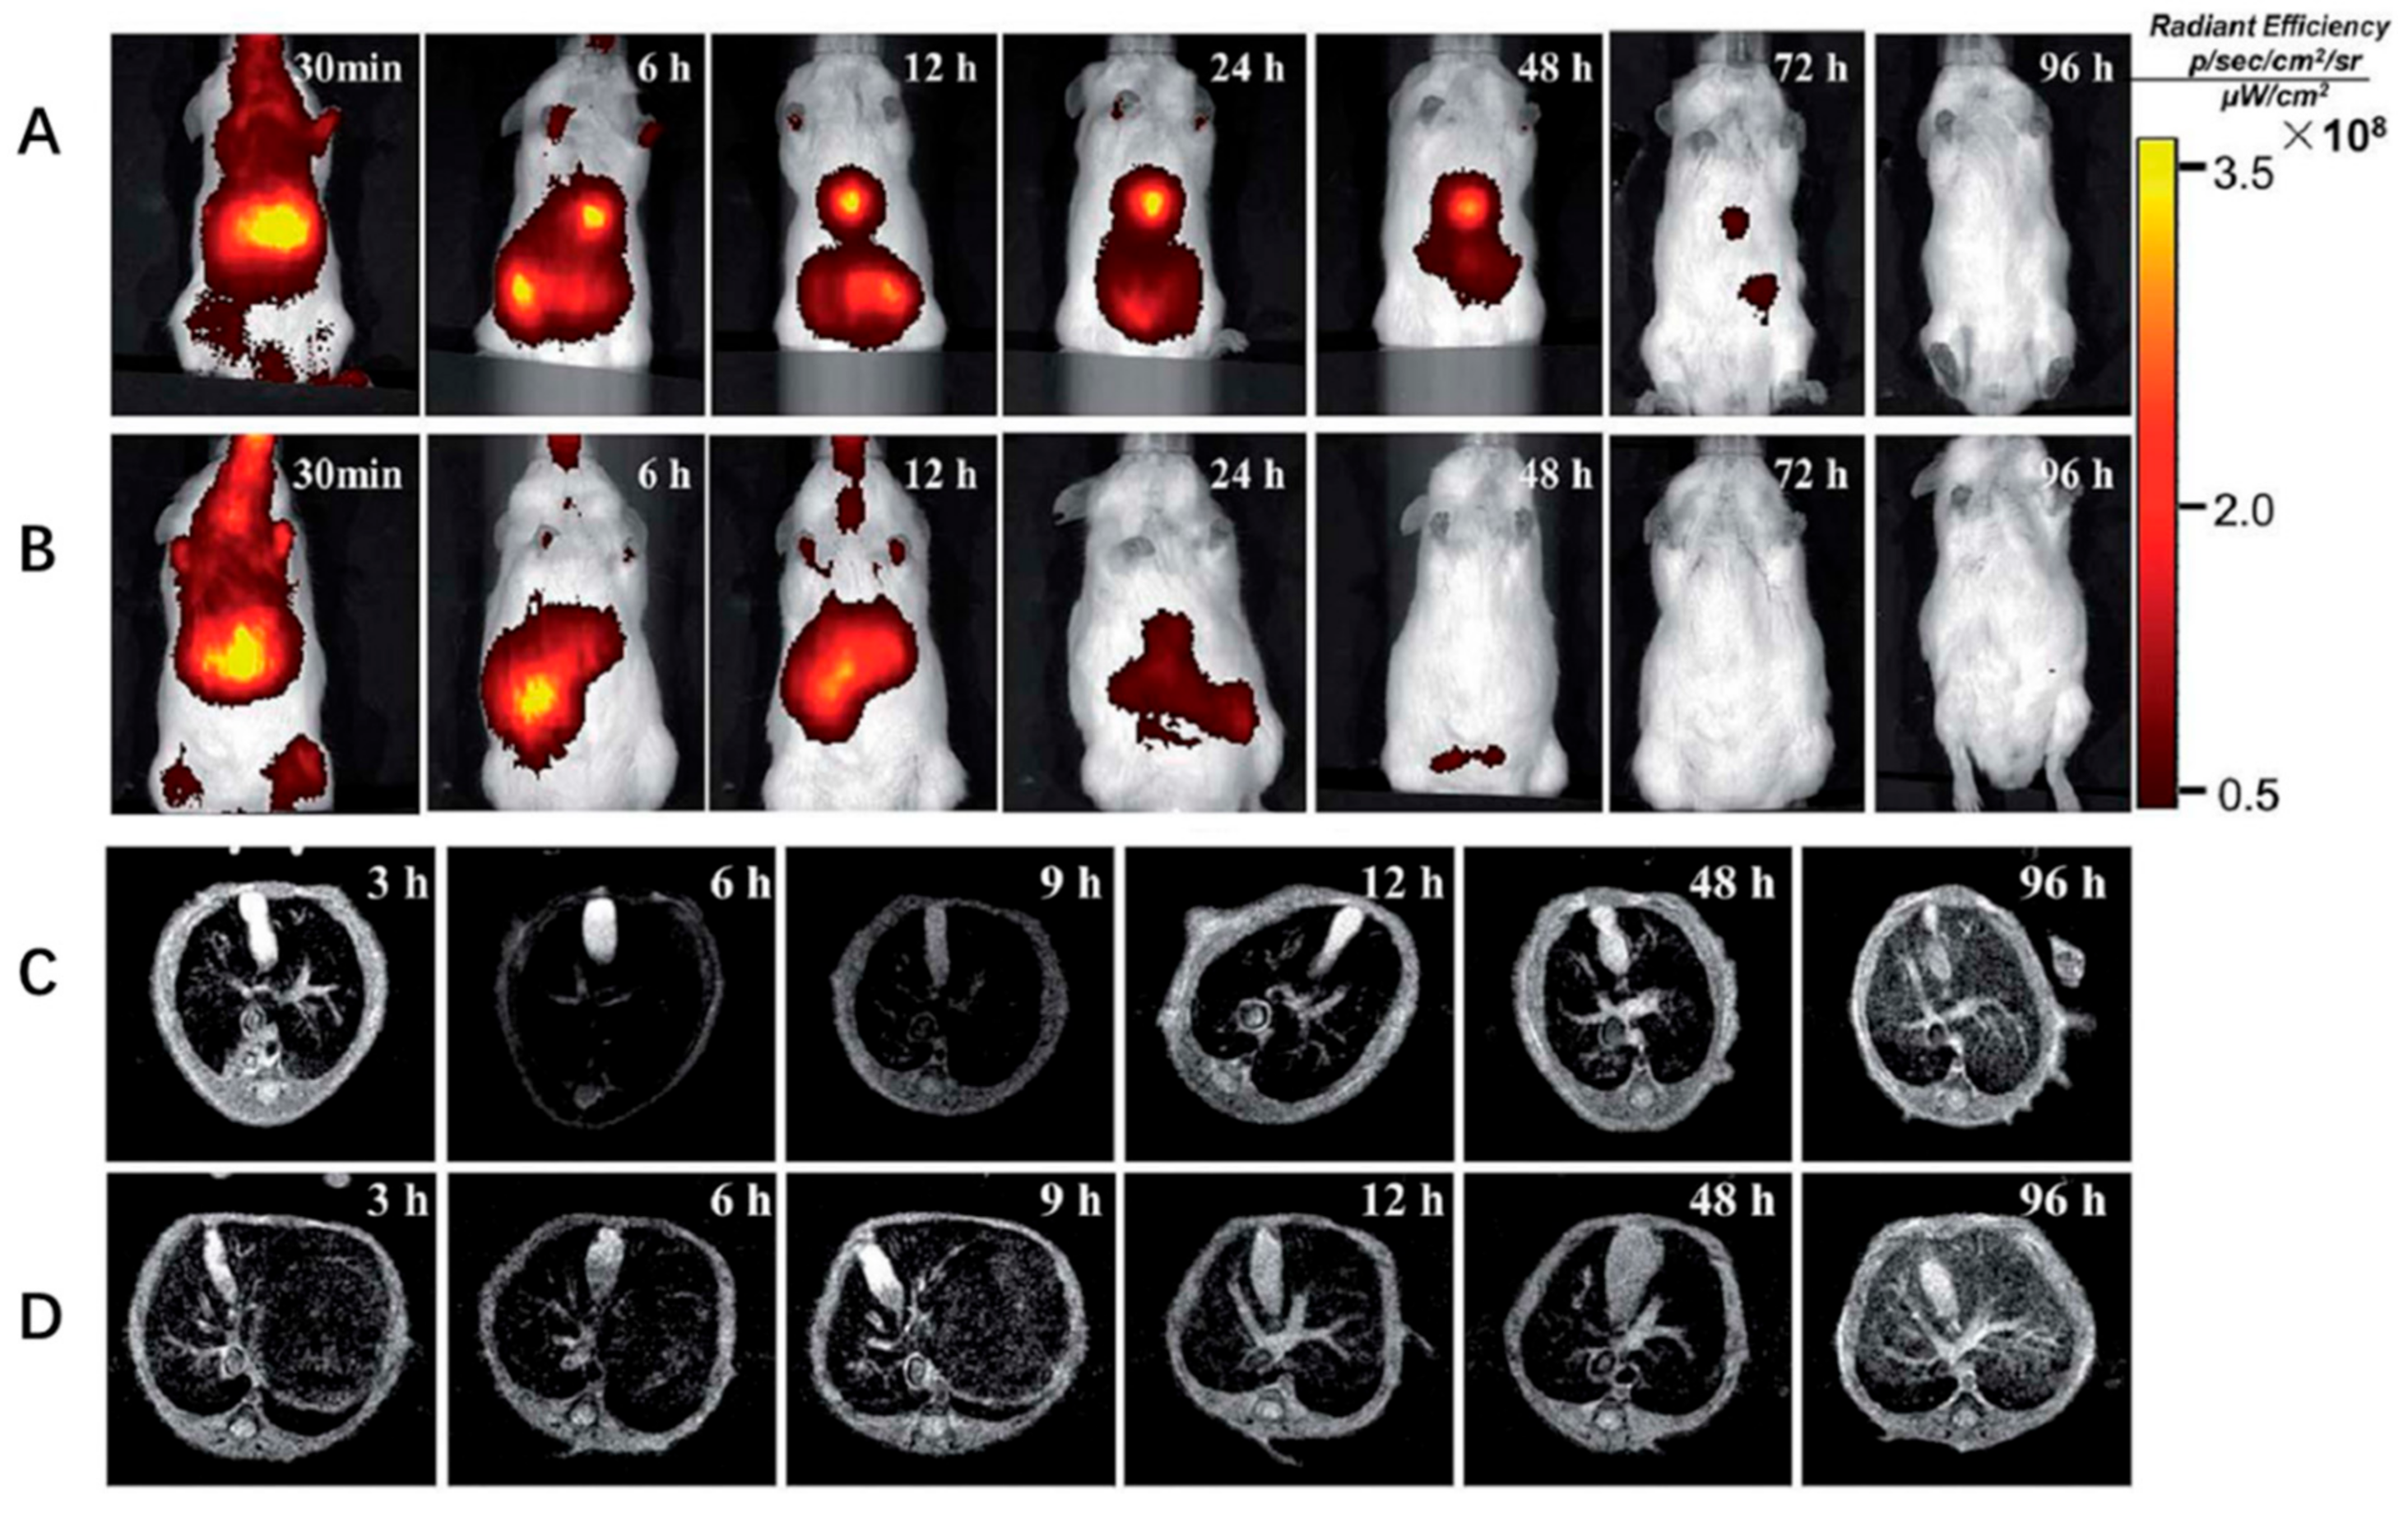

3. Nanomedicine in Liver Fibrosis Diagnosis